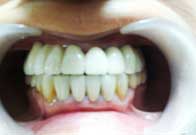

(6) Teeth Whitening

Before Treatment

After Treatment

Patient reported to us with the concern of Yellow teeth. Patient was conscious in social gatherings due to lack of confidence. Complete gum treatment and polishing was done for the patient followed by in office bleaching to achieve 2 shade whiter teeth. Home kit was a also delivered to the patient for maintenance as patient was coming from far.